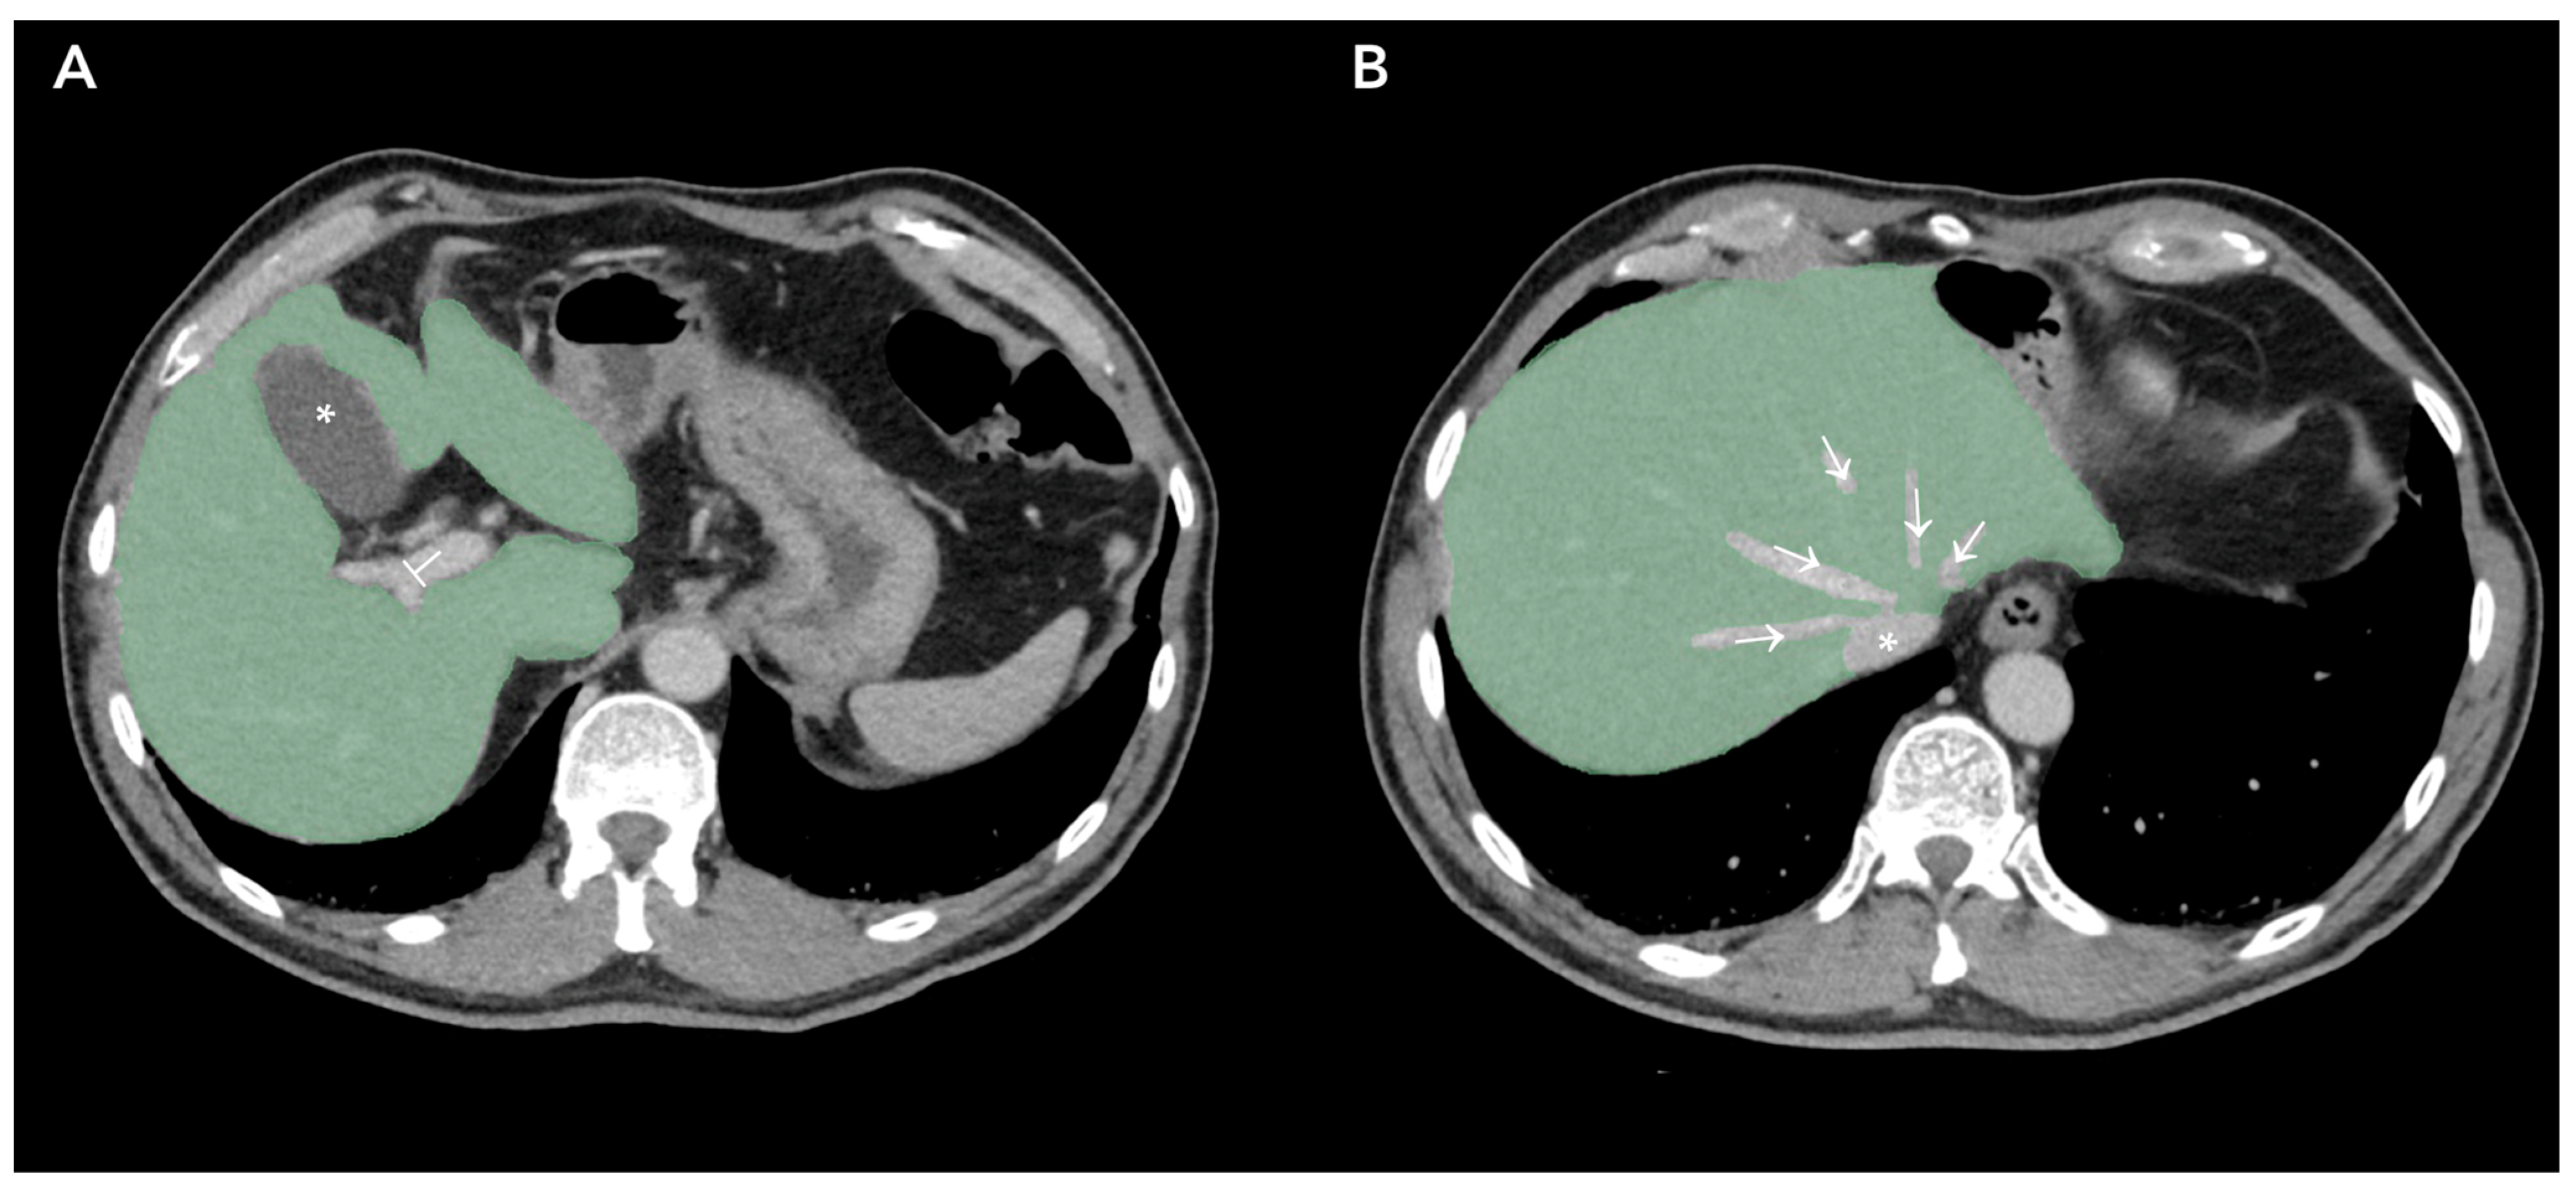

Figure 2 represents Regions of Interest (ROI) of apparently healthy liver parenchyma in patients affected by primary colorectal cancer without radiological evidence of liver metastasis.

Figure 2.

Regions of Interest obtained by Contrasted-Enhanced Computed Tomography slices of patients affected by Colorectal Cancer. (A), liver parenchyma marked green, gallbladder (*) and portal vein (⊥) exclusion; (B), liver parenchyma marked green, suprahepatic veins (→) and inferior vena cava (*) excluded.